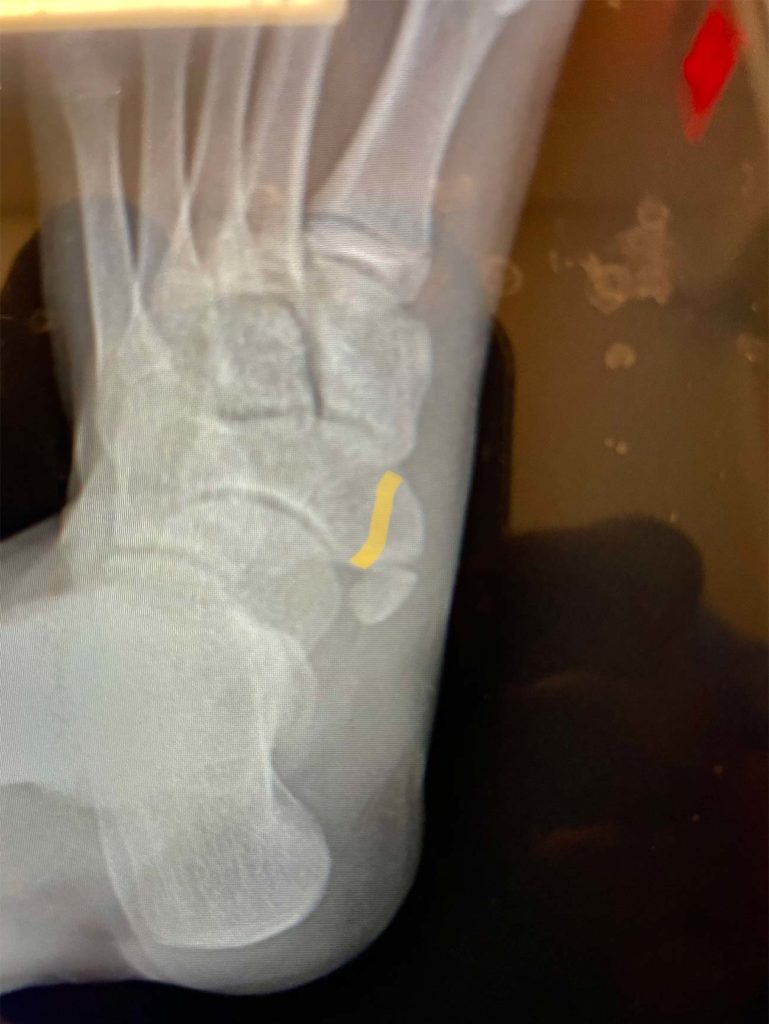

Accessory navicular bone on plain Xray in 5 cases; case 1 (type II Accessory Navicular Excision Protocol The surgery involves a number of steps: Once patients with ans become symptomatic, they. the accessory navicular (an) is a common accessory ossicle of the foot. General anaesthec, nerve block and iv anbiocs. Once patients with ans become. the accessory navicular (an) is a common accessory ossicle of the foot. acessory navicular is a common idiopathic condition. Accessory Navicular Excision Protocol.